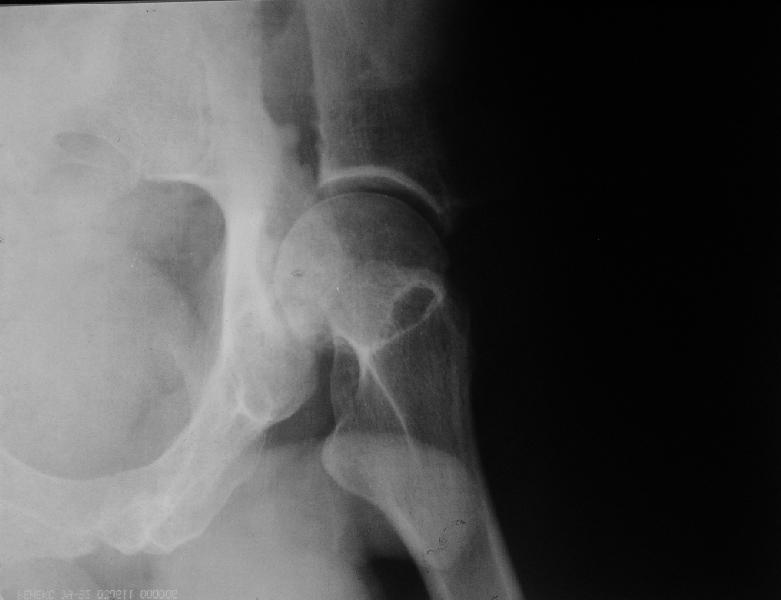

мужчина, 43 лет, получил травму в январе 2001 года. Лечился консервативно, в соседней области: скелетное вытяжение 6 недель, далее в кокситной гипсовой повязке 2 месяца. С декабря 2001 года ходит без дополнительной опоры, с компенсацией имеющегося укорочения - 4 сантиметра. С марта этого года беспокоят боли, усиливающиеся после умеренной физической нагрузки, возникающие в задних отделах таза и переходящие в область тазобедренного сустава. По данным ретгенографии и компьютерной томографии у больного имеется несросшийся высокий двухколонный перелом вертлужной впадины. Заранее спасибо.

Выхода нет- только замена сустава.